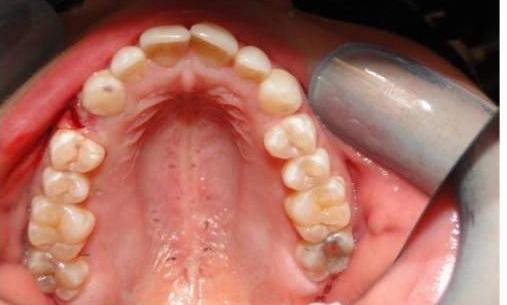

This adult patient had a baby tooth that never fell out, which stuck out like a sore thumb! We started by first removing the baby tooth, leaving the large gap seen in the "before" photo. With Invisalign, we were able to close this gap completely and also fix the mild crowding of their teeth.